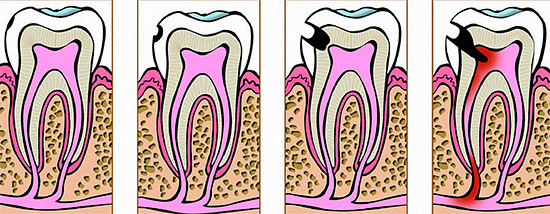

L'immagine mostra le principali fasi di sviluppo della carie dentale:

Sotto l'influenza di fattori cariogeni, la dentina viene distrutta molto più facilmente dello smalto, e quindi lo sviluppo della carie media e la sua transizione verso il decadimento profondo di solito avvengono abbastanza rapidamente.

Con la carie profonda, come suggerisce il nome, gli strati profondi di dentina sono interessati fino alle aree vicino alla polpa. Se la polpa stessa è interessata, la pulite inizia con dolore acuto e il rischio di infiammazione parodontale.

L'immagine mostra cosa succede quando la carie raggiunge la polpa e porta alla sua infiammazione: